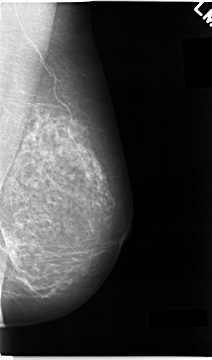

C_0043_1.LEFT_MLO

LEFT_MLO LINES 4672 PIXELS_PER_LINE 2744 BITS_PER_PIXEL 12 RESOLUTION 50 NON_OVERLAY